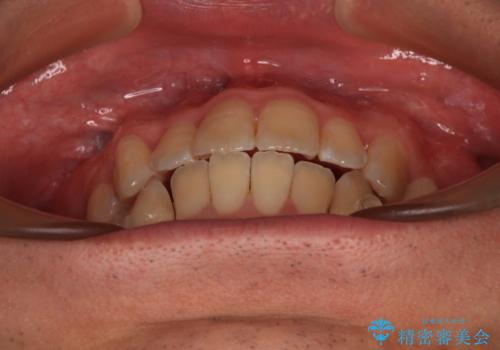

オープンバイトをインビザラインで矯正治療

- 前歯の開咬を気にして来院された患者様です。

開咬の治療は、前歯を閉じるように動かすとともに、上下臼歯を圧下(骨内にめり込ませる)させることで進めて行きます。

インビザラインは臼歯の圧下を効果的に行えるため、インビザラインを用いて矯正治療を行うこととしました。

オープンバイトは舌の突出癖により誘発され、治療後も突出癖が残っている容易に後戻りしてしまいます。

治療期間を短縮するためにも、舌突出癖の改善が極めて重要となります。

特にインビザラインではIPRという歯と歯の間を削る処置を多用するため、後戻りによりスペースが生じやすくなるため、治療初期段階での舌のトレーニングが必須となります。